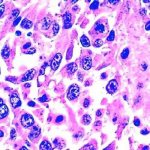

Tendon rupture is a traumatic injury to these anatomical elements. Most often, a tendon rupture occurs in the leg, since this is where the greatest load falls. A tendon rupture occurs when there is traumatic injury to the connective tissue portion of the muscles that attach to bones and muscles.

A tendon injury is a common injury in which the integrity of the tendons is compromised due to a cut or tear. Due to their wide prevalence, open injuries to the tendons of the hand and fingers are of greatest clinical importance. A distinctive feature of such injuries is the lack of independent fusion, caused by muscle contraction and the formation of significant diastasis between the separated tendon fragments. Without treatment, the outcome is loss of function of the corresponding muscles, impaired movement and, as a consequence, limitation or loss of ability to work.